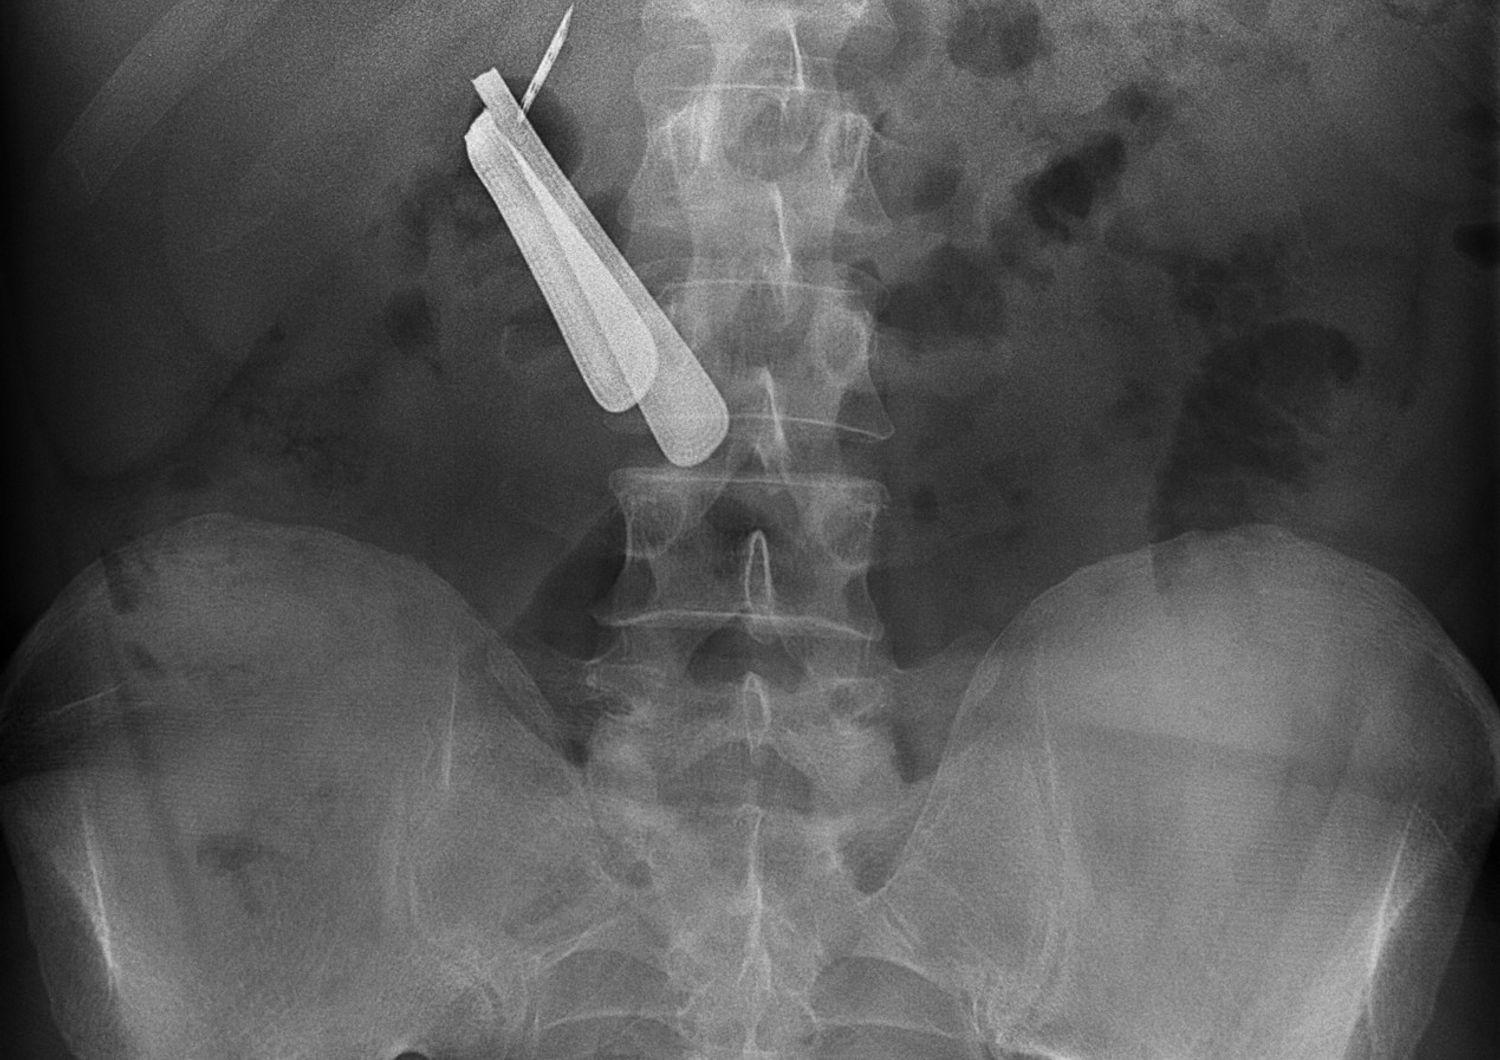

AGI - Più di un chilo di chiodi e viti nello stomaco di un uomo. Li hanno recuperati i chirurghi dell'ospedale universitario di Klaipede dove l'uomo si era presentato in preda a forti dolori. A quanto pare, l'uomo aveva smesso di bere alcolici e nell'ultimo mese ingeriva chiodi e viti, alcuni lunghi 10 centimetri.

Il chirurgo Sarunas Dailidenas lo ha definito un "caso unico". L'intervento è durato tre ore e l'uomo adesso è in osservazione ma sembra essere fuori pericolo. La notizia è stata data dalla tv pubblica lituana LRT che ha mostrato il vassoio chirurgico colmo degli oggetti metallici.